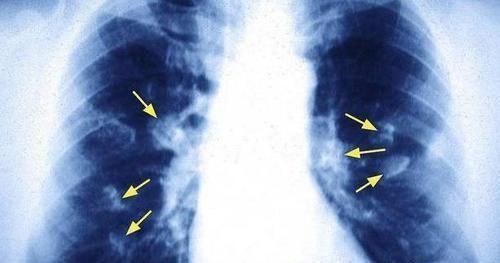

●呼吸总是表现急促:

日常生活中,倘若你感觉自己的呼吸十分急促,那么还请提高警惕。这种情况的出现,是由于肺癌肿瘤已经影响到了呼吸系统,从而让呼吸通道出现了堵塞,这样就让空气无法顺畅地进入到体内,最后让患者出现呼吸困难的情况。另外当肺癌细胞组织,入侵到了体内的一些淋巴细胞组织,甚至是静脉血管,那么也是很容易会引起呼吸困难的情况出现。

文章插图